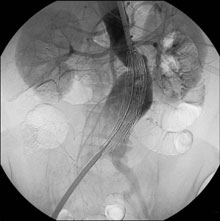

Patient mit Aortenaneurysma nach früherem unilateralem aortofemoralem Bypass, anhaltendem Nikotinabusus und alkoholtoxischer Leberzirrhose. Wegen reanimationspflichtiger Kontrastmittelreaktion bei früherer Angiographie nur Nativ-CT und MR-Angiographie.

Versorgung mit einem Anaconda-Stentgraft.

Intraoperative Angiographie mit Kohlendioxid.